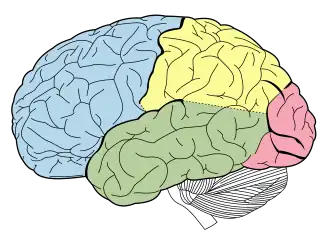

Frontal lobe epilepsy (FLE) is a neurological disorder that is characterized by brief, recurring seizures arising in the frontal lobes of the brain, that often occur during sleep.[1] It is the second most common type of epilepsy after temporal lobe epilepsy (TLE), and is related to the temporal form in that both forms are characterized by partial (focal) seizures.[2]

Due to the difference in brain processing and function as well as various surface anatomy landmarks, the frontal lobes have traditionally been divided into two major areas known as the precentral cortex and prefrontal cortex.

Precentral cortex

The precentral cortex (Brodmann area 6) is an area of the frontal cortex that is located directly anterior to the central sulcus and includes both the primary motor cortex and the supplementary motor area.[6] Inputs that project to both of these areas arise from a variety of locations in the brain that integrate sensory stimuli including the primary motor cortex, the thalamus and corticospinal projections.[6] These two areas along with several other main functional areas control both the preparation of motor movement as well as the execution of movements. These main functional areas are crucial to the development of the motor related symptoms associated with frontal lobe epilepsy focally when seizures are located within these defined areas.[10] The major functional areas include:

Prefrontal cortex